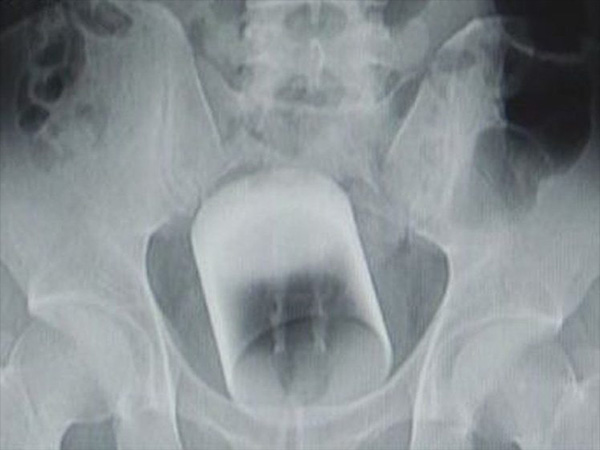

ಚೀನಾದ ಓರ್ವ ವ್ಯಕ್ತಿಗೆ ಆಗಿದ್ದೂ ಇದೇ! ಕಾಮದಾಟದಲ್ಲಿ ಏನೋ ಹೊಸ ಪ್ರಯೋಗ ನಡೆಸಲು ಹೋಗಿ ಎಡವಟ್ಟಾದ ಬಳಿಕ ಈ ಪುರುಷನನ್ನು ಆಸ್ಪತ್ರೆಗೆ ಕರೆತಂದು ವಿಲಿವಿಲಿ ಒದ್ದಾಡುತ್ತಿದ್ದವನ ನೋವಿಗೆ ಕಾರಣವೇನೆಂದು ವೈದ್ಯರು ಪರಿಶೀಲಿಸಿದಾಗ ಅವರಿಗೆ ಜೀವಮಾನದ ಅಚ್ಚರಿ ಕಾದಿತ್ತು. ಈತನ ಗುದದ್ವಾರದಲ್ಲಿ ಎಂಟಿಂಚಿನ ಗಾಜಿನ ಕಪ್ ಒಂದನ್ನು ತೂರಿಸಲಾಗಿತ್ತು....ಮುಂದೇನಾಯಿತು ನೋಡೋಣ...

ಯಾವುದೋ ಪ್ರಯೋಗ ಮಾಡಲೆಂದು ಹೋಗಿ ಗುದದ್ವಾರದಲ್ಲಿ ಎಂಟಿಂಚಿನ ಗಾಜಿನ ಕಪ್ ಒಂದನ್ನು ತೂರಿಸಲಾಗಿದ್ದು ಬಳಿಕ ಹೊರತೆಗೆಯಲಾಗದೇ ಹಾಗೇ ಉಳಿದು ಹೋಗಿತ್ತು. ಕೊಂಚ ಹೊತ್ತು ಕಾದು ನೋಡುವ ಎಂದು ಎರಡು ದಿನ ಇತ ಕಾದ ಬಳಿಕ ನೋವು ತಾಳಲಾರದಷ್ಟು ಹೆಚ್ಚಿದ್ದರಿಂದ ಕಡೆಗೂ ಆತ್ಮೀಯರ ನೆರವಿನಿಂದ ಈತನನ್ನು ಆಸ್ಪತ್ರೆಗೆ ಕರೆತರಲಾಗಿತ್ತು. ಆದರೆ ಅಷ್ಟು ಹೊತ್ತಿಗಾಗಲೇ ಈತನ ಹಿಂಭಾಗ ಭಾರೀ ಒತ್ತಡದಿಂದ ಊದಿಕೊಂಡಿದ್ದು ನೋವು ಅಪಾರವಾಗಿತ್ತು.

ರೋಗಿಯ ದೇಹವನ್ನು ತಪಾಸಿಸಿ ನೋವಿಗೆ ಕಾರಣ ಏನೆಂದು ಹುಡುಕಿದ ವೈದ್ಯರಿಗೆ ಈತನ ಗುದದ್ವಾರದಲ್ಲಿ ಇಡಿಯ ಒಂದು ದೊಡ್ಡ ಎಂಟಿಂಚಿನ ಗಾಜಿನ ಕಪ್ ಒಂದನ್ನು ತೂರಿಸಲಾಗಿದ್ದುದು ಕಂಡುಬಂದಿತ್ತು. ಈಗ ವೈದ್ಯರಿಗೆ ನಿಜವಾಗಿಯೂ ಗೊಂದಲ ಹಾಗೂ ಗಾಬರಿ ಉಂಟಾಗಿತ್ತು. ಏಕೆಂದರೆ ಗಾಜು ಸುಲಭವಾಗಿ ಪುಡಿಯಾಗುವ ವಸ್ತುವಾಗಿದ್ದು ಇದರ ಮೇಲೆ ಯಾವುದೇ ಒತ್ತಡ ಹೇರಿದರೂ ಇದು ದೇಹದ ಒಳಗೇ ಸ್ಫೋಟಗೊಂಡಂತೆ ಒಡೆದು ಗಾಜಿನ ಚೂರುಗಳೆಲ್ಲಾ ದೇಹದ ಮುಖ್ಯ ಅಂಗಗಳಿಗೆಲ್ಲ ಚುಚ್ಚಿ ಹರಿದು ಪರಿಸ್ಥಿತಿಯನ್ನು ವಿಷಮವಾಗಿಸುತ್ತಿತ್ತು. ಇದು ಸಾವಿಗೂ ಕಾರಣವಾಗಬಹುದು.

ಶಸ್ತ್ರಕ್ರಿಯೆ ಅನಿವಾರ್ಯವಾಗಿತ್ತು

ತಕ್ಷಣವೇ ಕಟುನಿರ್ಧಾರ ತೆಗೆದುಕೊಂಡ ವೈದ್ಯರ ತಂಡ ಕೂಡಲೇ ಈ ವ್ಯಕ್ತಿಯ ಹಿಂಭಾಗಕ್ಕೆ ಅರವಳಿಕೆಯ ಇಂಜೆಕ್ಷನ್ ನೀಡಿ ಮರಗಟ್ಟಿಸಿದರು. ಆದರೂ ಅಪಾಯವಿಲ್ಲದಂತೆ ಕಪ್ ಅನ್ನು ಹೊರತೆಗೆಯುವ ಭರವಸೆಯಂತೂ ಆ ಹೊತ್ತಿನಲ್ಲಿ ಯಾವ ವೈದ್ಯರೂ ನೀಡಲು ತಯಾರಿರಲಿಲ್ಲ. ಏಕೆಂದರೆ ಗಾಜು ಅತಿ ನಯವಾಗಿದ್ದು ಜಾರುತ್ತಿದ್ದ ಕಾರಣ ಹಿಡಿತಕ್ಕೇ ಸಿಗುತ್ತಿರಲಿಲ್ಲ. ಬಳಿಕ ಶಸ್ತ್ರಕ್ರಿಯೆ ನಡೆಸಿ ಗಾಜು ಒಡೆಯದಂತೆ ಸುರಕ್ಷಿತವಾಗಿ ಹೊರತೆಗೆಯಲಾಯ್ತು. ಬಳಿಕ ಈ ವ್ಯಕ್ತಿ ನಿಧಾನಕ್ಕೆ ಚೇತರಿಸಿಕೊಳ್ಳುತ್ತಿದ್ದಾನೆ. ಆದರೆ ಈ ಕಪ್ ತನ್ನ ದೇಹದೊಳಗೆ ಹೇಗೆ ಬಂದಿತ್ತು ಎಂಬ ಪ್ರಶ್ನೆಗೆ ಆತ ಉತ್ತರ ನೀಡಬಯಸದೇ ಗೌಪ್ಯತೆ ಕಾಪಾಡಿಕೊಂಡಿದ್ದಾನೆ. ಈತನ ದೇಹದೊಳಗೆ ಕಪ್ ಹೋಗಿದ್ದಾದರೂ ಹೇಗೆ? ಏನು ಸಂಭವಿಸಿರಬಹುದು? ಈ ಬಗ್ಗೆ ನಿಮ್ಮ ಕಲ್ಪನೆಯನ್ನು ಬರೆದು ಖಂಡಿತಾ ತಿಳಿಸಿ. ಇದಕ್ಕಾಗಿ ಕೆಳಗಿನ ಕಮೆಂಟ್ಸ್ ಭಾಗವನ್ನು ಬಳಸಿಕೊಳ್ಳಿ.